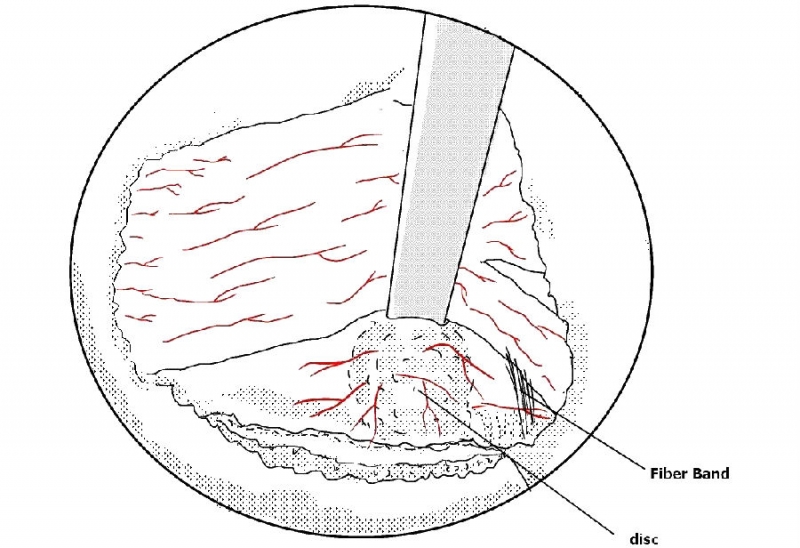

11. 用UBE拉钩牵开神经根;

12. 突出间盘表面的预止血和神经根周围束带的切除;

13. 使用髓核钳摘除突出的髓核组织;